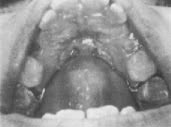

This was a girl 10 years and 8 months of age (Fig. 6).

On the upper right side there was about 2mm of space between the lateral and the deciduous first molar, with only a bit of extra space on the anteriors. Cuspids were pretty well blocked out. Lower cuspids were overlapping 2-2½mm. So, we took out all four first bicuspids, put in a palatal button and waited. In a year's time, look what drift has done (Fig. 7).

In this case I probably would have been better off without the palatal button and losing a little space. Look at the lower E space. The anteriors have aligned perfectly, yet there is still that much space. The difference between a deciduous second molar and a bicuspid is tremendous. Many men don't realize how much E space is. We were taught that there is 1.7mm of E space or leeway. But, the average deciduous second molar is 10mm and the average bicuspid is 7mm. That's a lot of difference Deciduous first molars are almost 8mm wide and first bicuspids average 7mm, so there is almost another millimeter there. If both first and second deciduous molars are in place, you can have almost 4mm of extra space on each side. The deciduous cuspid is about 5mm and the permanent cuspid 7, so you lose 2mm on that. Many times you will see a case in which the deciduous cuspid has been removed and you'll see 2-3mm space between the lateral and deciduous first molar. You'll think that this case is really going to be crowded. You extract bicuspids and you've got a 7mm space to close afterward and you wonder what happened.

Fig. 6 Case 2. Before treatment.

Fig. 7 Case 2. Demonstrating one year of drift following extraction.